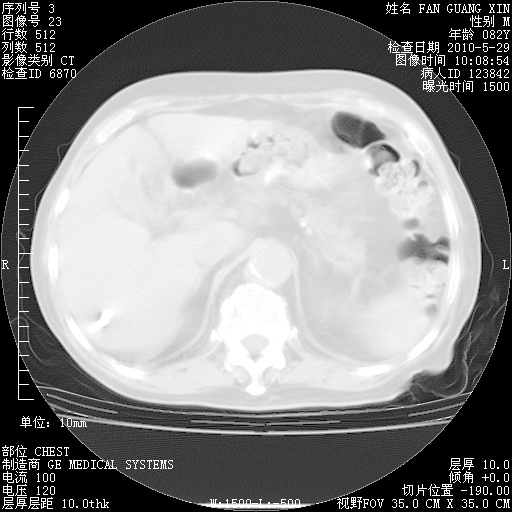

再治疗10天后的肺部CT 纵膈窗

阅读此次胸部CT,肺间质渗出性改变较入院时有吸收。目前从体温、白细胞、中性分叶明显增高,肯定存在细菌感染(发生医院感染哦,若无消化道及泌尿系统等感染的依据,肺部感染可能大)。若你院头孢哌酮舒巴坦钠耐药率较高,同意你的方案,若48小时体温仍高,可考虑使用碳青霉稀类抗菌药物,同时可予超声雾化、注意滴数时加大液体量。白蛋白33.30g/L较低哦,需加强营养等支持治疗。

从白细胞总数和中性比例看好像合并感染。肺部纹理好像比上次多,支气管炎?其他感染?